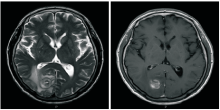

患者, 男性, 70岁, 因“ 肺癌术后4个月, 头痛呕吐1周” 于2014-10-06入院。患者2014年5月因咳嗽、痰中带血就诊于外院, 2014-05-16胸部+上腹部增强CT提示:右肺下叶肿物, 大小约21 mm× 5 mm, 纵隔淋巴结未见肿大; 头颅MRI提示:双侧额顶叶白质多发缺血灶, 副鼻窦炎; 支气管镜提示:右下叶基底段见出血, 盲检未发现癌细胞。2014-05-28 电视胸腔镜手术切除右下肺叶+纵隔淋巴结清扫术, 病理提示:中至低分化腺癌, 癌组织未侵犯脏层胸膜, 可见脉管内癌栓, 未见神经束侵犯, 支气管残端未见癌, R2(0/3)、R4(0/1)、7(0/2)、11(0/6)、12(0/1)、13(0/1); CK7(+), TTF-1(+), CK5/6(-), P63部分细胞弱阳性; 术后诊断为右下肺中低分化腺癌 (pT1bN0M0, Ⅰ a期); 分子病理:EGFR(测序法)阴性, ALK(FISH)阴性, c-MET(FISH)未见扩增; ROS1(FISH)阴性, K-ras阴性, P-TEN(FISH)无缺失。2014-10-02 出现头痛、呕吐, 2014-10-08收入我院。既往史:高血压病史20余年(3级, 极高危); 无吸烟史和粉尘接触史; 无肿瘤家族史。体格检查: T: 36.5℃, P:92 次/分, R: 20 次/分, BP: 142/90 mmHg, PS=1, 全身浅表淋巴结未触及, 头面部无水肿, Horner 征阴性, 上腔静脉综合征阴性, Pancoast 征阴性, 胸廓无畸形, 双肺呼吸音清, 未闻及干湿罗音, 脊柱四肢无异常, 关节无肿痛, 无杵状指。神经系统检查无异常。辅助检查:2014-10-08胸片:右肺术后改变, 右侧胸膜增厚、少量胸腔积液; 2014-10-08 头颅MRI:右枕叶可见类圆形异常信号灶, 约20 mm× 18 mm, 病变周围有脑水肿。见图1。

刘春玲(放射科主治医师):患者2014-05-16在外院行头颅MRI检查, 从影像学来看未见明确的转移病灶, 而在2014-10-08头颅MRI中可以看到右侧枕叶新出现病灶, 在T1相呈高信号, 可能有出血情况, 周围伴有水肿, 结合患者既往肺癌病史, 考虑为脑转移。见图2。